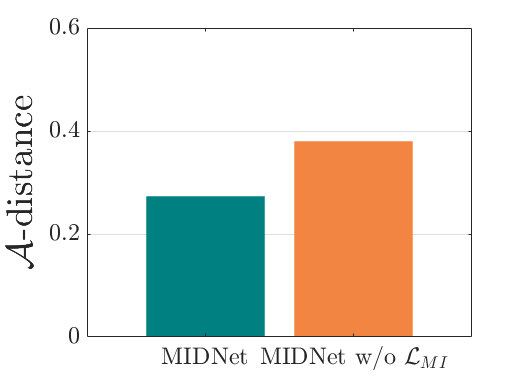

We compare the -distance of categorical features and domain features. Fig. 5 (a) shows that domain difference is higher in domain features than in categorical features. This indicates that domain features contain more domain information whereas categorical features are more domain-invariant. Fig. 6 shows the t-SNE plot of categorical features in both domains for MIDNet. From Fig. 6 (a), we observe that the categorical features learned by MIDNet enable the anatomical classification. Fig. 6 (b) shows that the learned categorical features are domain-invariant.

The experimental results of the state-of-the-art and the ablation study are shown in Table. II. In this table, we observe that the MIDNet model outperforms all the state-of-the-art methods on the most important test data for average F1-score, recall and precision. MIDNet+ performs better than MIDNet on and , demonstrating that metric learning is important and efficient for improving classification performance on images whose features have been observed during training. In the ablation study, MIDNet outperforms other variant models, especially MIDNet w/o , MIDNet w/o and MIDNet w/o , illustrating the effectiveness of all proposed components in MIDNet. In addition, Fig. 7 (a) shows that the -distance of MIDNet w/o is higher than that of MIDNet. This demonstrates that mutual information disentanglement () contributes to learn domain-invariant categorical features.